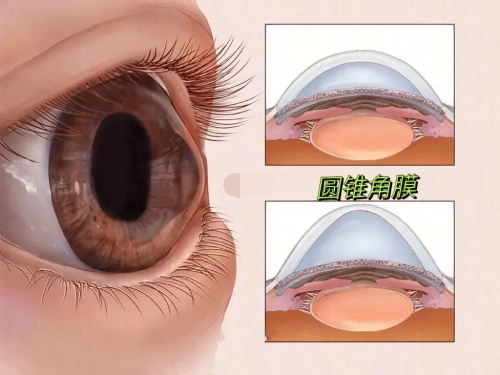

特殊眼部条件适配:

角膜散光患者:定制化散光矫正模块,减少术后残留散光。

瞳孔较大者:无衍射环设计降低瞳孔散大时的视觉干扰。

晶体材料抗撕裂性提升,术后晶体移位风险降低,适合角膜条件复杂或瞳孔较大的患者。